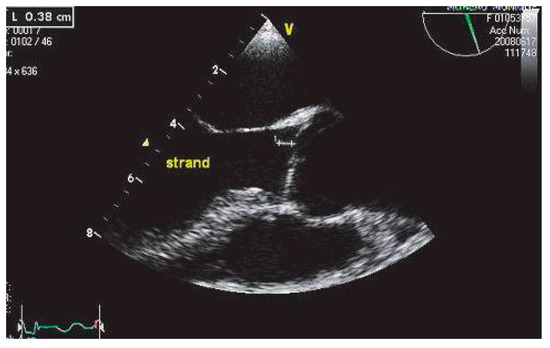

Echocardiographie et Sources Cardiaques d'embolie

Cardioembolic stroke is the second cause of ischemic stroke, with a high rate of morbidity and mortality. Echocardiography, mainly transesophageal echocardiography, is very useful for the diagnosis and risk stratification of the various potential car...